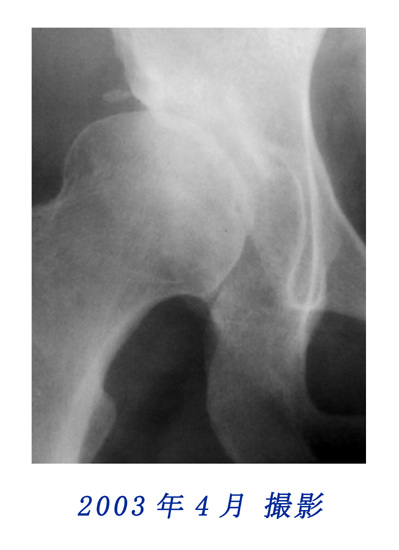

右股関節の変化(部分拡大)

2003年と2005年に撮影されたレントゲン写真中、右の股関節にも顕著な変化を認められました。

右股関節の変化比較用

2003年と2005年のレントゲン写真の股関節部を拡大して重ねました。写真にカーソルを重ねると2003年と2005年の写真が入れ替わります。股関節の変化を観察してください。